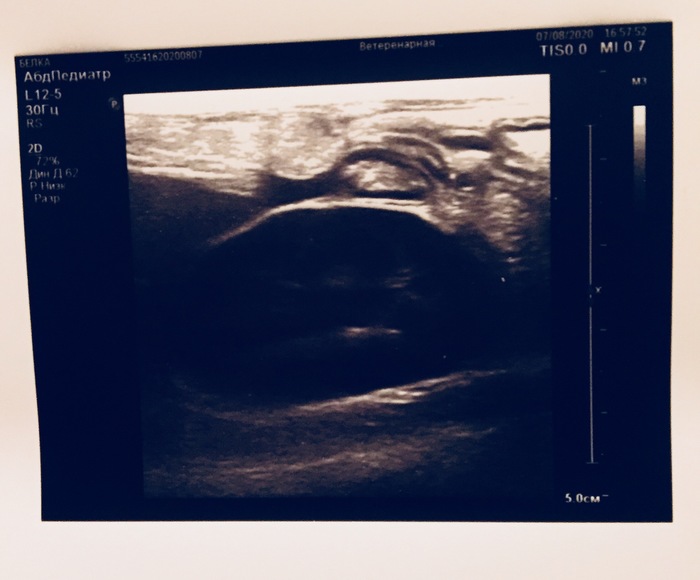

Продолжение поста «Заболела наша Белка, подобранная на улице. Жидкость в брюшной полости и гематома печени. Завтра вечером будут готовы анализы»1

Всем привет от Белки. Пришли анализы крови. Все более менее. Анализы нетипичны для ФИП. Очень надеемся, что это печень. Если это так, то потребуется срочная операция по удалению гематомы. Но это лечится довольно успешно и кошки с этим живут. Сейчас я капаю Белку дома. Приходится изобретать способы для подвешивания бутылки с раствором. Завтра будет готов анализ жидкости. Сейчас у неё опять температура 39.8. Скорее всего, будем давать жаропонижающее. Белка ест и пьёт сама.

Заболела наша Белка, подобранная на улице. Жидкость в брюшной полости и гематома печени. Завтра вечером будут готовы анализы1

Всем привет. Несколько дней назад Белке стало плохо - поднялась температура. Она стала тяжело дышать. Стала хуже есть. Сидеть в напряжённой позе.

Сегодня @LazyMouse26 повезла Белку в клинику на обследование. Сделали УЗИ, рентген, откачали жидкость из живота (100 мл). Увидели небольшое количество жидкости в легких. Жидкость отправили на два анализа - ФИП и на бактерии. Завтра вечером будет готов результат.

На части печени ясно видна гематома.

Каков результат? У нас два варианта, один из которых ФИП, другой - гематома.

Мы очень надеемся, что это гематома. Ее можно будет удалить и Белка поправится.